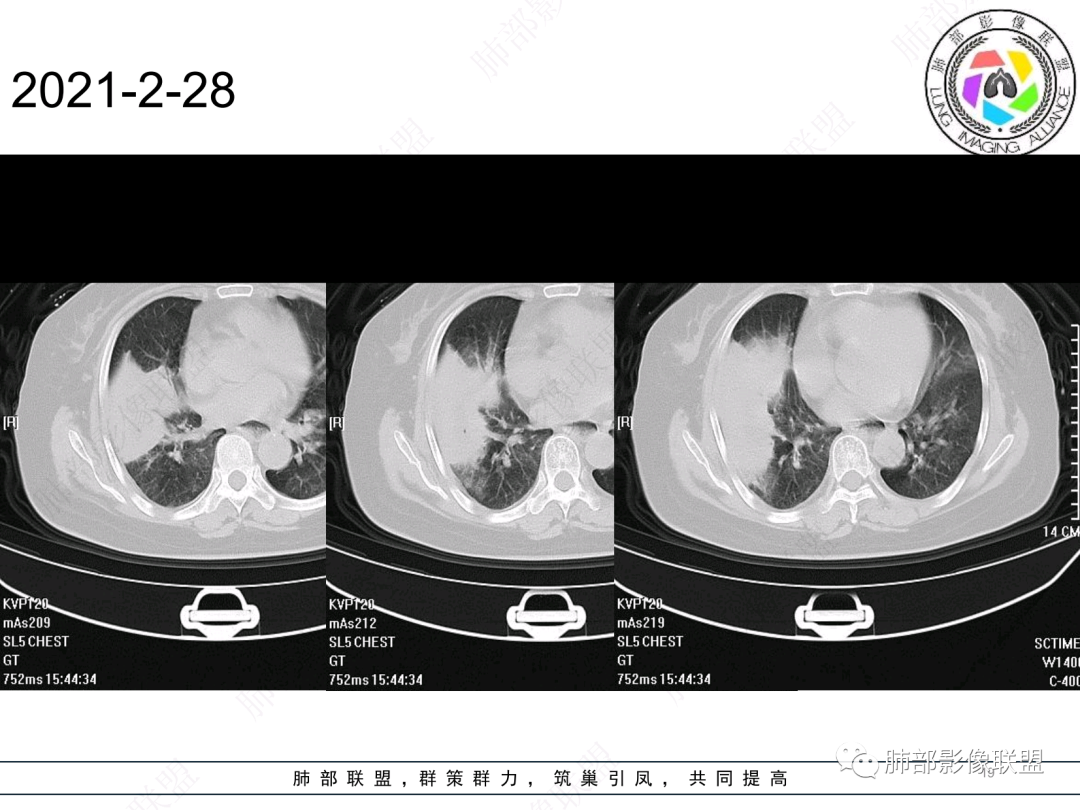

慢性咳嗽,抗炎复查无好转,原右肺中叶实边,外侧段支气管开口阻断,复查无好转,逐渐向下叶外前基底段融合形成大肿块,边缘膨隆,密度不均匀,坏死轮廓不清,内血管束破坏,累及中轴间质厚,外围分布,方向恶性,与炎性肉芽肿鉴别,隐球荚膜抗原先排查!

女,74岁,咳嗽咳痰加重一周入院,右肺中叶大片实变影,边界清晰,病灶内密度不均匀,右肺中叶支气管变窄,增强扫描病灶明显强化,考虑恶性病变能,鉴别肺脓肿。

右肺中叶实变,支气管开口阻断,边缘膨隆,密度不均匀,坏死边界清晰,胸膜累及,。一般抗感染治疗无效。考虑恶性。

老年女性患者,慢性病程,两次活检均提示炎性病变,胸部CT:右肺中叶大片实变密度影,边界尚清楚,部分收缩,部分膨隆,内部有低密度坏死,坏死边界清楚,无明显结节感,无分割,总体考虑炎性病变,机化性肺炎,NTM,慢性肺脓肿,鉴别:恶性,腺癌

右肺中叶大片实变,内见大片的坏死,中叶外侧段支气管阻塞,相邻胸膜增厚,间隔约四个月后复查,发现低密度坏死内可见气泡影,老年人,反复迁延不愈的病变要考虑恶性,首先考虑腺癌伴感染。鉴别慢性脓肿。

右肺胸膜下实变,跨叶,形态不规则,局部边缘膨隆,中叶支气管外侧段进入后阻塞伴不张,不均匀强化,其内坏死边界欠清晰,复查无吸收,考虑腺癌,鉴别慢性炎症伴脓肿

右肺大片状高密度灶,跨叶,密度不均,边缘膨隆,支气管阻塞,粘液栓,不均匀强化,其内坏死边界欠清晰,复查无吸收,考虑腺癌,鉴别慢性炎症,脓肿

胸部CT:右肺中下叶大片实变影,界清,边缘膨隆为主,中叶外侧段支气管截断。增强不均匀强化,边缘可见血管影迂曲模糊,内见条带状低密度影。治疗后病变进展。考虑恶性,鳞Ca?鉴别TB、OP。

老年女性,慢性病史,炎性指标稍高,肿标正常,右中下肺大片实变,跨叶生长,边界清,收缩力差,膨隆生长为主,支气管杵状截断,均匀强化,其内坏死边界清,可见悬浮气泡,整体观察,病灶膨隆生长为主,邻近肺野无播散灶,形态单一,尽管慢性病史,影像不支持OP和TB,支气管截断呈杵状,肿标正常,均匀强化,虽是高龄患者,诊断恶性肿瘤有点牵强,综和分析,首选炎性病变放线菌感染,其次考虑低度恶性占位炎机母。